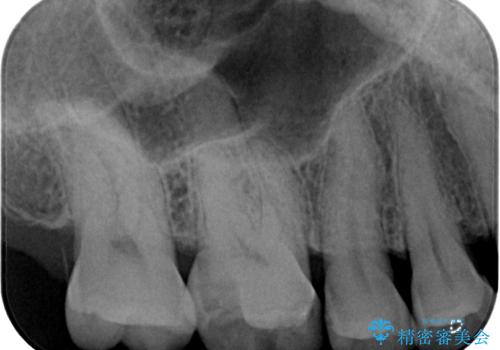

- メンテナンスで通っていただいている患者様で、銀歯が外れたので診てほしいとのことで来院された患者様です。以前にも何度か同部位が外れる度につけ直している状況でした。又、遠心口蓋側咬頭がかけている状態でなるべく歯を削らずセラミックの詰め物を入れたいとのことでハイブリッドアンレーで治療していくことになりました。

拡大鏡視野下で虫歯、古いプラスチック(コンポジットレジン)を除去し、ハイブリッドアンレーに適した形に整えました。

歯と歯茎の間に圧排糸と言われる糸を入れてシリコーン印象材にて型どりをしました。